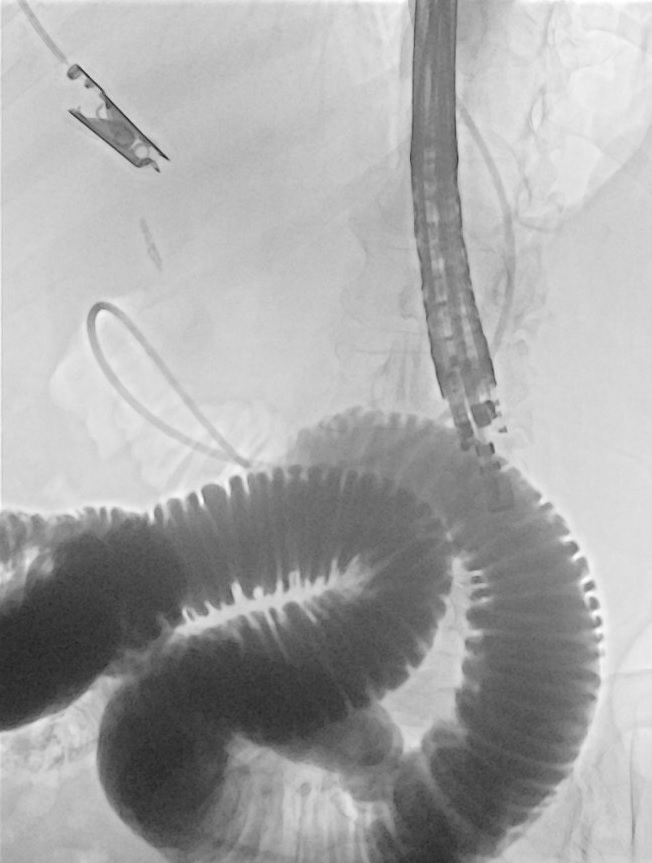

@DouglasAdlerMD

Douglas G. Adler MD, FASGE, FACG, AGAF

3 days

Now THAT is a big common bile duct stone! #gitwitter #surgery @Stentingwoman @EUSandEndoscopy @DavidDiehlMD